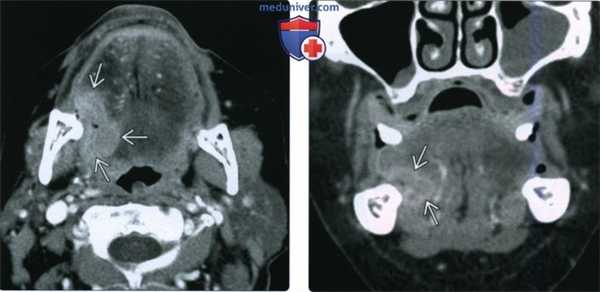

(Слева) При аксиальной КТ с КУ у курильщика 59 лете жалобами на болезненное уплотнение в языке, появившееся пять месяцев назад, в задних боковых отделах языка визуализируется изъязвленное объемное образование неправильной формы, интенсивно накапливающее контраст. На более каудальных томограммах был также выявлен единичный лимфоузел второго уровня.

(Справа) При корональной КТ с КУ определяется неравномерное контрастное усиление язвы. Отсутствуют признаки глубокой инфильтрации наружных мышц языка, опухоль не достигает средней линии. Была выполнена правосторонняя гемиглоссэктомия и модифицированная шейная лимфодиссекция, подтвердился ПКР T2N1 (третья стадия).